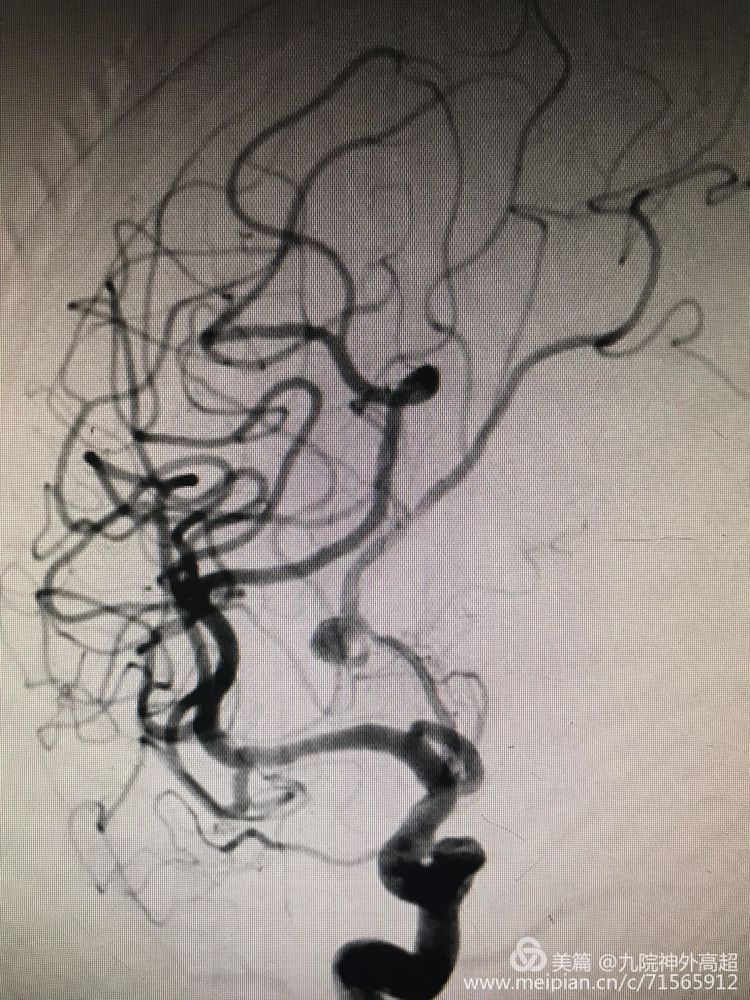

大脑前交通动脉瘤

动脉瘤栓塞完全